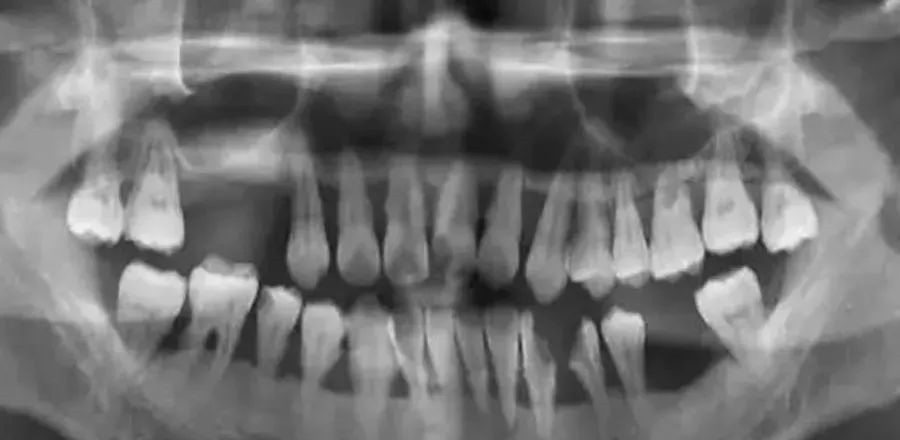

但接诊医生做完检查后直摇头,并告知:“你的全口牙齿种上得花二十多万元”,老吴整日茶饭不思,一直在纠结该怎么处理这一口牙齿,又思想斗争了半个月后,老吴好不容易下定决心花大价钱弄好自己这一口牙齿,然而,这次他又遭遇了晴天霹雳,因为他的牙龈肿的肿、猥琐的猥琐,在种植之前必须处理好牙周问题,于是被转到牙周科,接诊的医生按例给他拍了X光片。

片子显示牙槽骨已经差不多丢失殆尽,这意味着即使他想种植牙齿也未必可以,医生跟他说:“这就跟种树一样,没有土的话,能把树给种好吗?”这次,老吴彻底懵了,一个劲追问医生:“几十年来我连牙疼都没有过怎么一来就全完了呢?”医生告诉他:“这一切的问题都根源于牙周病,全中国有80%左右的人会得这种病,但多数人都没有重视其早期症状。”